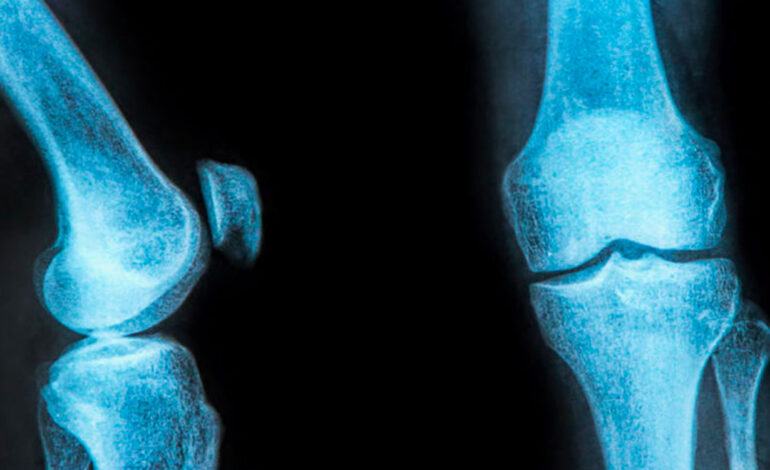

Une étude tunisienne a révélé que 25 % des femmes âgées de plus de 45 ans souffrent d’ostéoporose après la ménopause, selon la Professeure Kawthar Ben Abdelghani, Rhumatologue à l’Hôpital Mongi Slim.

L’ostéoporose chez les femmes ménopausées est une maladie « silencieuse » dans de nombreux cas, car les personnes atteintes ne présentent pas de symptômes ou de douleurs dans les premiers stades, a déclaré la même source à la TAP. Les changements hormonaux jouent aussi un rôle majeur dans l’affaiblissement des os, les rendant plus vulnérables aux fractures. Des facteurs génétiques, comme le fait d’avoir un père ou une mère ayant subi des fractures pelviennes, peuvent aussi augmenter la probabilité que les enfants développent la maladie.